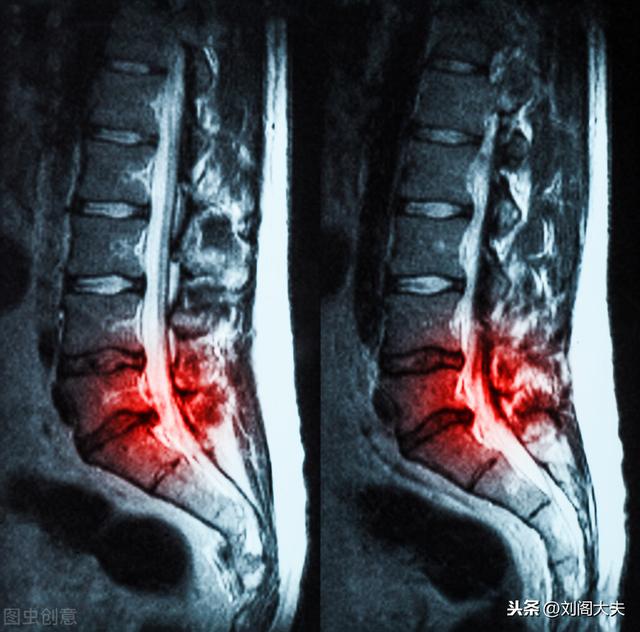

腰椎椎間板ヘルニア 腰椎椎間板ヘルニアとは?これは私たちが最初に理解しなければならない、私たちは皆、人が私たちの背骨を形成するために積み重ねられた骨を持っていることを知っているが、私たちはああ骨を粉砕させることができないので、人類の進化は、この柔らかいクッションをディスクに参加したが、人間はしばしば労働の体重負担の摩耗や破損、時間の経過とともに、椎間板のこの柔らかいクッションは、対応する組織や神経の圧縮の外に実行されます対応する病理学的症状が表示されます、そのような腰痛、脚の痛み、脚のしびれ、脚の木、深刻な不快感が腸に発生し、坐骨神経の圧迫は、脚の症状が表示されます。脚の痛み、脚のしびれ、脚の木、深刻な尿や便の不快感、坐骨神経の圧迫は、脚の症状が表示されます。

もちろん、解剖学的な側面から、腰椎椎間板ヘルニアと呼ばれるものを説明する必要があります。腰椎椎間板ヘルニアはより一般的な病気の一つで、主に腰椎椎間板の髄核、線維性環状組織、軟骨板などの部分、特に髄核が、外的要因の役割の中で様々な程度の退行性変化があり、椎間板の線維性環状組織が破裂し、髄核組織が破裂した場所から突出したり、後方や脊椎管に脱出したりします。髄核が破裂部位から後方または脊柱管に突出または剥離することで、隣接する脊髄神経根が刺激または圧迫され、腰痛、しびれ、片方または両下肢の痛みなどの一連の臨床症状を引き起こします。腰椎椎間板ヘルニアの発生率は、腰椎4-5番と腰椎5-仙骨1番が最も高く、約95%を占める。